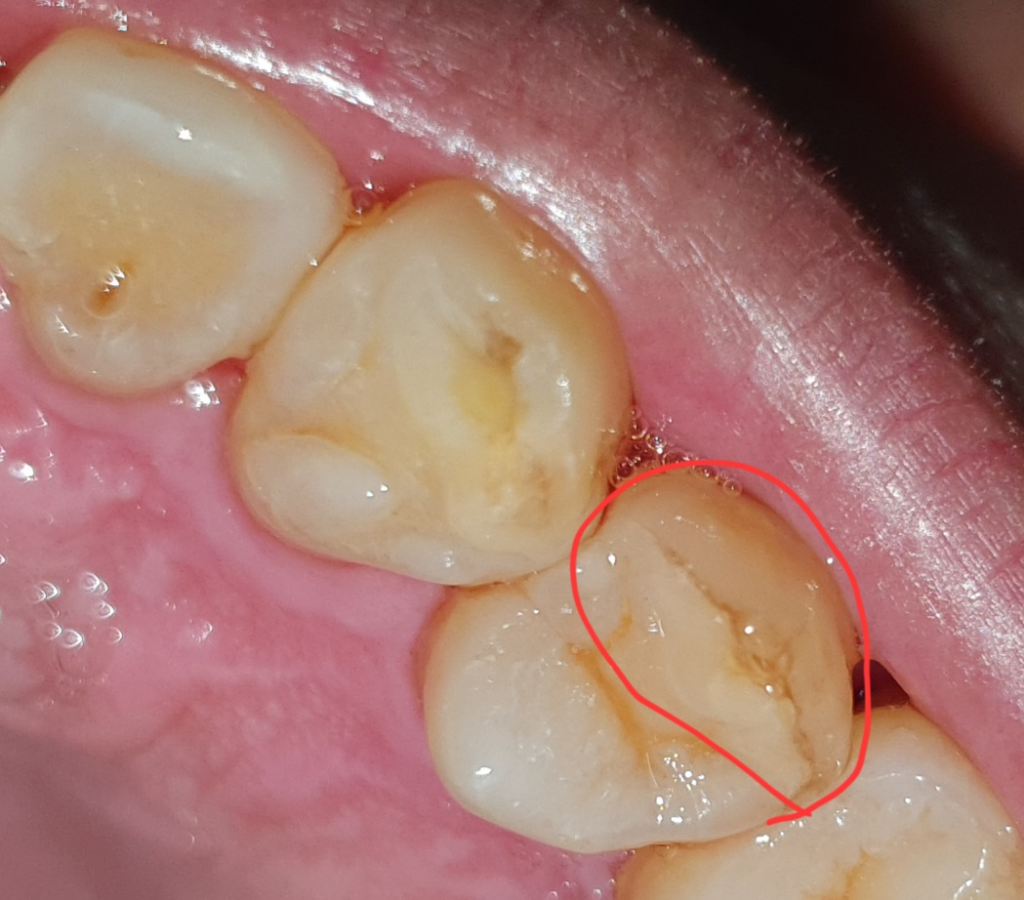

사진 상으로는 금이 갔는지 판단하기 어렵습니다. 여러가지 검사를 통해서 해당 부위의 금 정도를 판단해야 하며 미세한 금이라면 단순히 사진이나 검사만으로는 힘들 수 있습니다. 정확한 판단을 위해서는 치과 방문 후 검사를 해야 합니다.